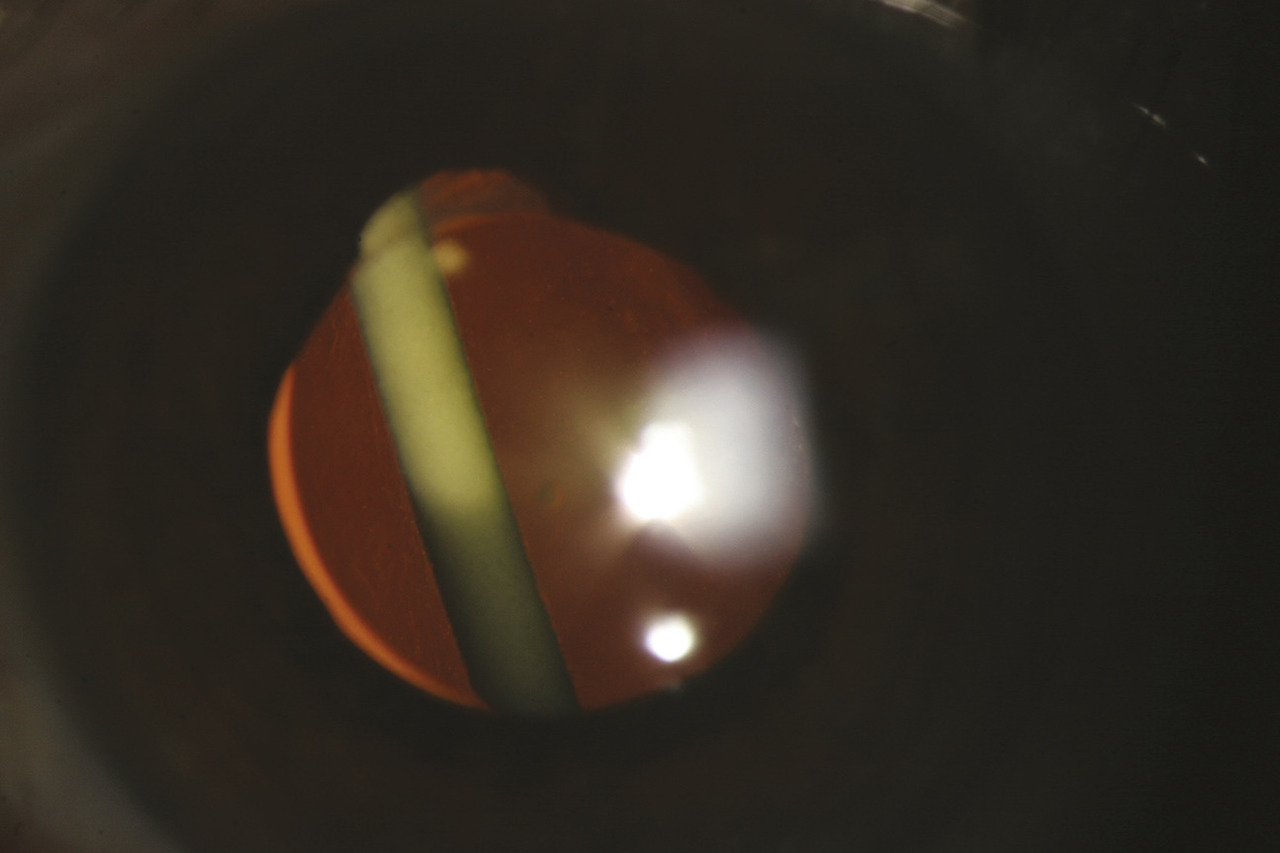

Les uvéites antérieures sont celles dont le traitement est habituellement le plus simple, car le site primitif de l’inflammation est accessible à un traitement par collyres. La corticothérapie topique est le socle du traitement de ces uvéites. Celle-ci est associée à une dilatation de la pupille par des collyres à l’atropine, ou à ses dérivés d’action plus brève, pour prévenir la formation de synéchies (adhérences d’origine inflammatoire) entre la face postérieure de l’iris et la face antérieure du cristallin (fig. 1). Dans le domaine des uvéites antérieures, les innovations thérapeutiques concernent essentiellement les uvéites associées aux spondylarthrites chez des sujets porteurs de l’allèle HLA-B27.